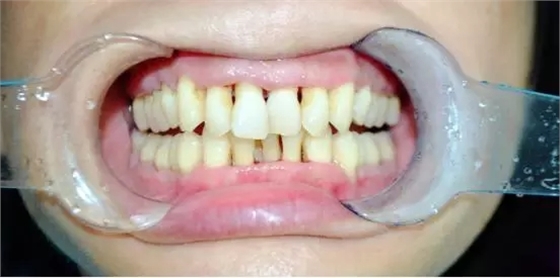

一周后陸小姐復(fù)診,

牙齦出血有好轉(zhuǎn),但患牙仍有松動,能夠發(fā)現(xiàn),齦乳頭萎縮,醫(yī)生繼續(xù)采用階段性牙周治療,慢慢讓牙齦紅腫消除,繼續(xù)常規(guī)消毒,齦下刮治,沖洗,上藥?;颊咝枰龊萌粘5目谇蛔o(hù)理。

半個月后

檢查:牙齒松動度緩解,牙齦邊緣無紅腫,無明顯探診出血